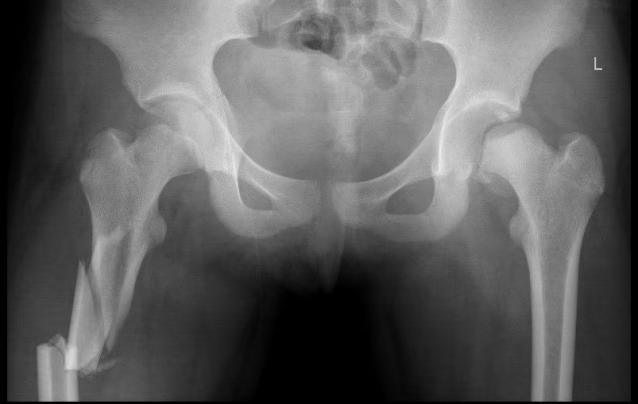

与此同时,小儿骨科·创伤骨科潘建宏主任第一时间带领团队对小张的病情进行了全面检查与评估,经诊断,明确了小张的骨折属于右侧股骨上段粉碎骨折,左侧股骨颈骺分离、Delbet分型Ⅰa型、Salter_ HarrisⅠ型骨骺损伤,骨折的股骨头骺端脱位于髋臼后侧。而这种骨折约占儿童所有骨折的万分之五,非常少见,并且手术难度大、风险大、预后差。

面对如此复杂且严重的伤情,潘主任立即组织全科进行讨论,在深入研究和综合分析,科室团队一致认为,经过股骨头骺端脱位出髋臼后侧,闭合复位不可行,应用外科脱位技术(SHD),既能最大程度保护骨折处血运、又能直视下复位,可吸收螺钉顺行固定后空心加压螺钉逆行加压固定,右侧股骨上段粉碎骨折应用青少年髓内钉固定。于是根据小张的具体情况,科室团队精心制定了一套科学、详尽的治疗方案。